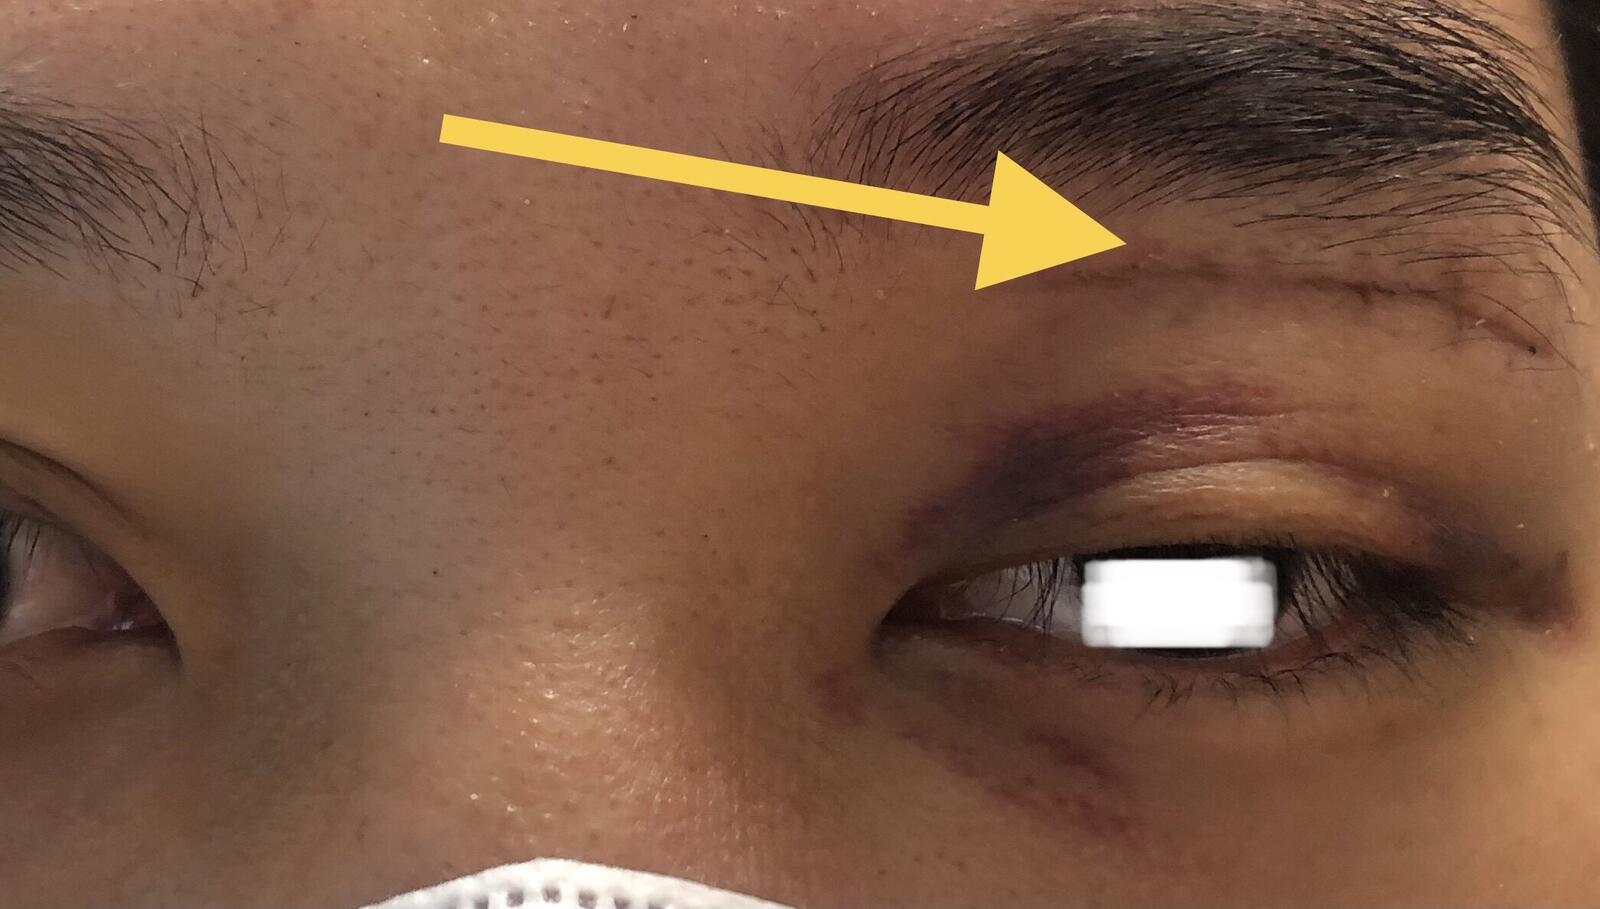

术后早期额部麻木,及上睑下垂属于术后正常情况,绝大部分均会逐渐好转。

术后上睑下垂绝大部分会逐步改善,必要的切口长度确保肿瘤完整摘除